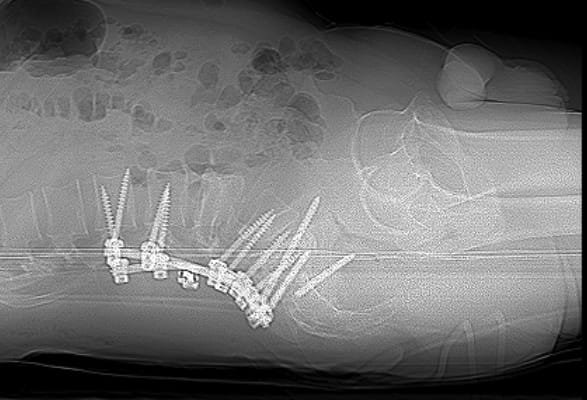

Усі повторні операції пов’язані з більшим ризиком ускладнень та потребують ретельного планування. «З одного боку це був цікавий випадок. З іншого – ми завжди допомагаємо нашим військовим з особливим задоволенням», - розповідає Олексій Леонтьєв. Склалося так, що у пацієнта було встановлено 6 гвинтів, з яких 1 поламався, 3 розхиталося і таким чином його хребет втратив опороздатність. Складність операції полягала і ще у тому, що зламану частину гвинта видалити практично неможливо і ставало питання про встановлення додаткових гвинтів та видалення тих що розхиталися. План був складений. На допомогу прийшли наші колеги (https://www.facebook.com/Implants.in.ua), які надали металоконструкцію, що була необхідна для пацієнта.

Це була складна операція. Вона тривала 7 годин. Розхитані та поломані гвинти було видалено, а також конструкцію було додатково укріплено ще гвинтами. Перепроведено тазовий гвинт. Також була виконана декомпресія корінця S1 що давав виражений больовий синдром.

Результати реоперації на наступних малюнках: